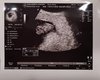

Masz fotke? Ile bejbik ma mm/cm ? [emoji16]Ja już po wizycie. Byłam wczoraj.

Wszystko jest ok [emoji16]. Słyszałam serduszko <3 [emoji7].

Dostałam skierowanie na badania prenatalne i umówiłam się już na 25.06.